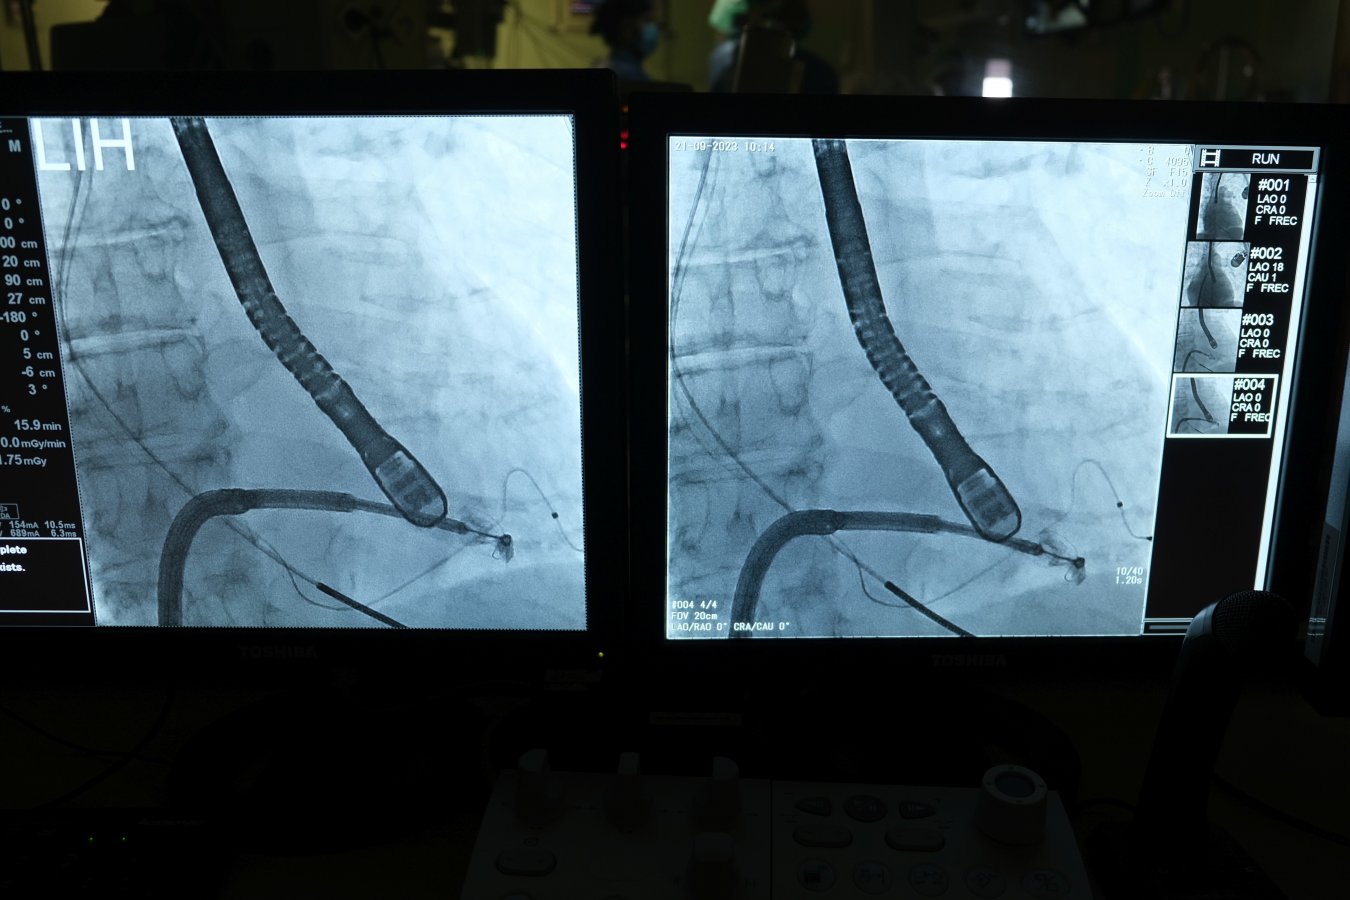

Zabieg przezcewnikowej naprawy zastawki mitralnej jest znacznie mniej inwazyjny. Pacjenci są poddawani narkozie. Następnie przez żyłę udową, przez prawy przedsionek, do lewego przedsionka wprowadza się specjalny cewnik. Zabieg polega na zszyciu za pomocą specjalnej zapinki obu płatków zastawki mitralnej w miejscu powstania niedomykalności.

Trudność zabiegu polega na chwyceniu, pod kontrolą echokardiografii przezprzełykowej, obu ciągle ruszających się płatków zastawki. Procedura wymaga wręcz zegarmistrzowskiej precyzji, a także idealnego zgrania zespołu operatorów i nawigacji echokardiograficznej.